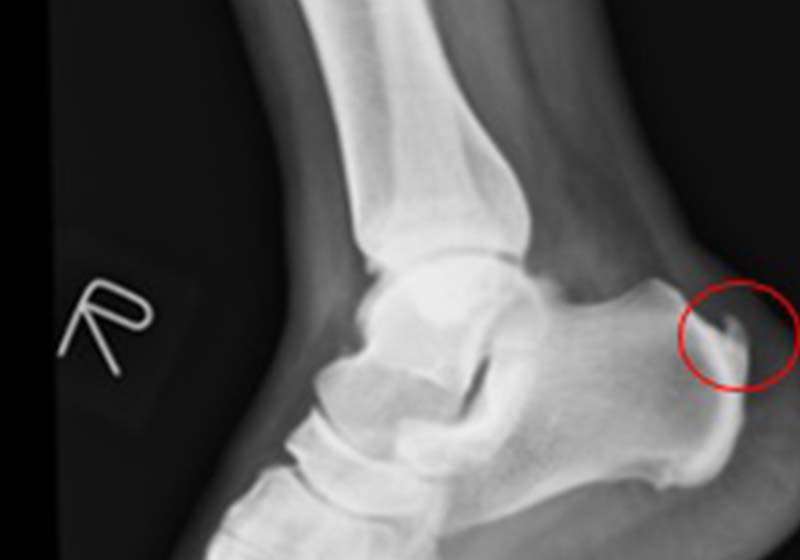

高市劉姓員警退休後陪伴高齡母親,種植竹筍過程突感足底疼痛,就醫治療兩年未見改善,經友人轉介七賢脊椎外科醫院骨關節科主任吳宗哲確診足跟骨骨刺,肇因阿基里斯肌腱過度拉扯,術後恢復正常生活。

吳宗哲說,跟骨骨刺可能出現疼痛、灼熱、腫脹等症狀,久站、運動傷害、肥胖、扁平足、高足弓等是好發族群,提醒足跟疼痛持續逾一週,建議就醫檢查治療。圖/七賢脊椎骨科醫院提供、文/高培德